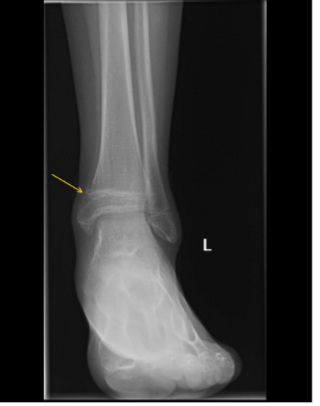

While awaiting evaluation, he sustained a Salter-Harris II fracture of the distal left tibia after tripping while using crutches (Figure 3).

Figure 3. X-ray of the left ankle with fracture through the medial tibial metaphysis and physis (yellow arrow) with periosteal reaction and osteopenia.